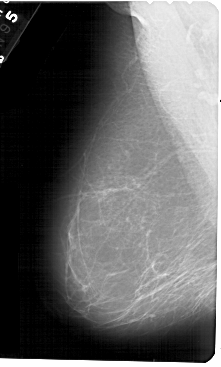

A_1604_1.RIGHT_MLO

RIGHT_MLO LINES 5491 PIXELS_PER_LINE 3361 BITS_PER_PIXEL 12 RESOLUTION 43.5 OVERLAY

FILE: A_1604_1.RIGHT_MLO.OVERLAY

TOTAL_ABNORMALITIES 1

ABNORMALITY 1

LESION_TYPE CALCIFICATION TYPE PLEOMORPHIC DISTRIBUTION CLUSTERED

ASSESSMENT 4

SUBTLETY 3

PATHOLOGY BENIGN